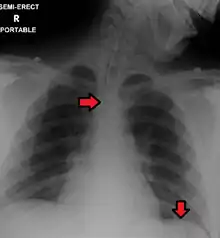

Great care must be taken to ensure that the tube has not passed through the larynx into the trachea and down into the bronchi. The reliable method is to aspirate some fluid from the tube with a syringe. This fluid is then tested with pH paper (note not litmus paper) to determine the acidity of the fluid. If the pH is 4 or below then the tube is in the correct position. If this is not possible then correct verification of tube position is obtained with an X-ray of the chest/abdomen. This is the most reliable means of ensuring proper placement of an NG tube.[8] The use of a chest x-ray to confirm position is the expected standard in the UK, with Dr/ physician review and confirmation. Future techniques may include measuring the concentration of enzymes such as trypsin, pepsin, and bilirubin to confirm the correct placement of the NG tube. As enzyme testing becomes more practical, allowing measurements to be taken quickly and cheaply at the bedside, this technique may be used in combination with pH testing as an effective, less harmful replacement of X-ray confirmation.[9] If the tube is to remain in place then a tube position check is recommended before each feed and at least once per day.